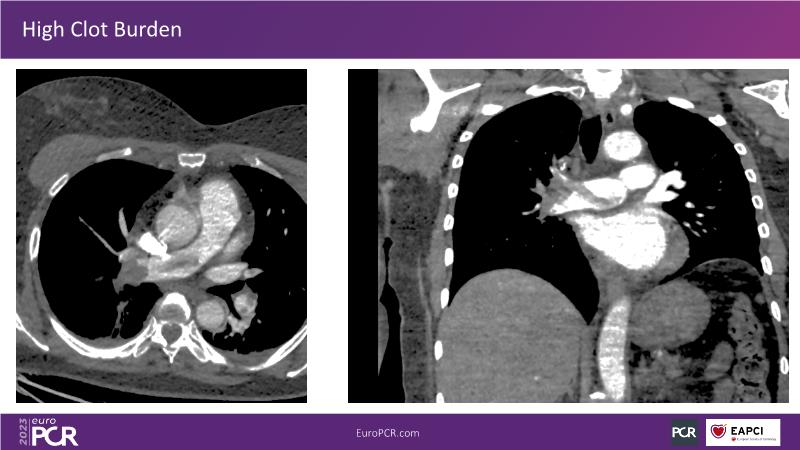

Primary percutaneous pulmonary intervention (pPPI) of acute pulmonary embolism with computer-aided mechanical aspiration

Summary

As there is a need for more awareness, training and data on primary percutaneous pulmonary intervention, watch this session to learn from shared pioneering experience!